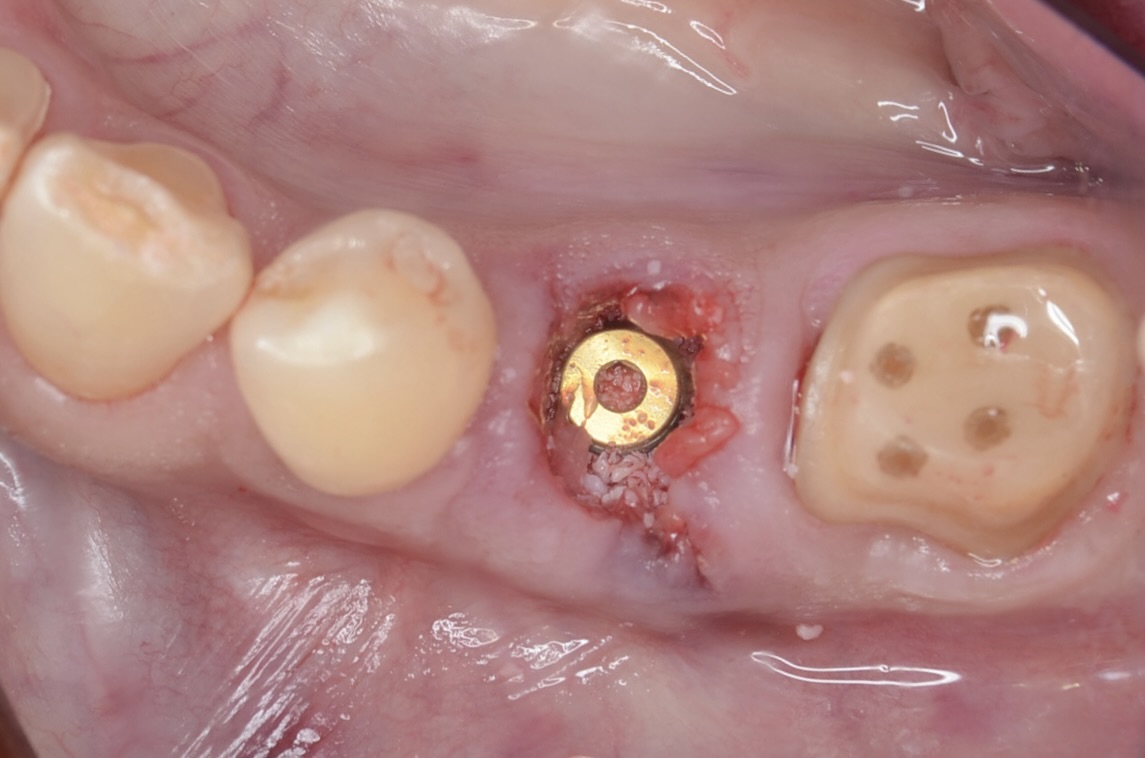

インプラント埋入

抜歯と同時にインプラントを埋入。インプラントと骨の隙間にはコラーゲンや骨補填材を詰めています。 -